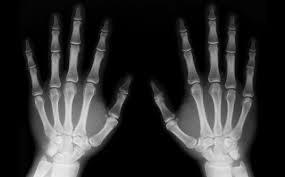

Imágenes

Formato DICOM

Cabecera

Cuerpo de datos de imagen

Puede tener múltiples fotogramas